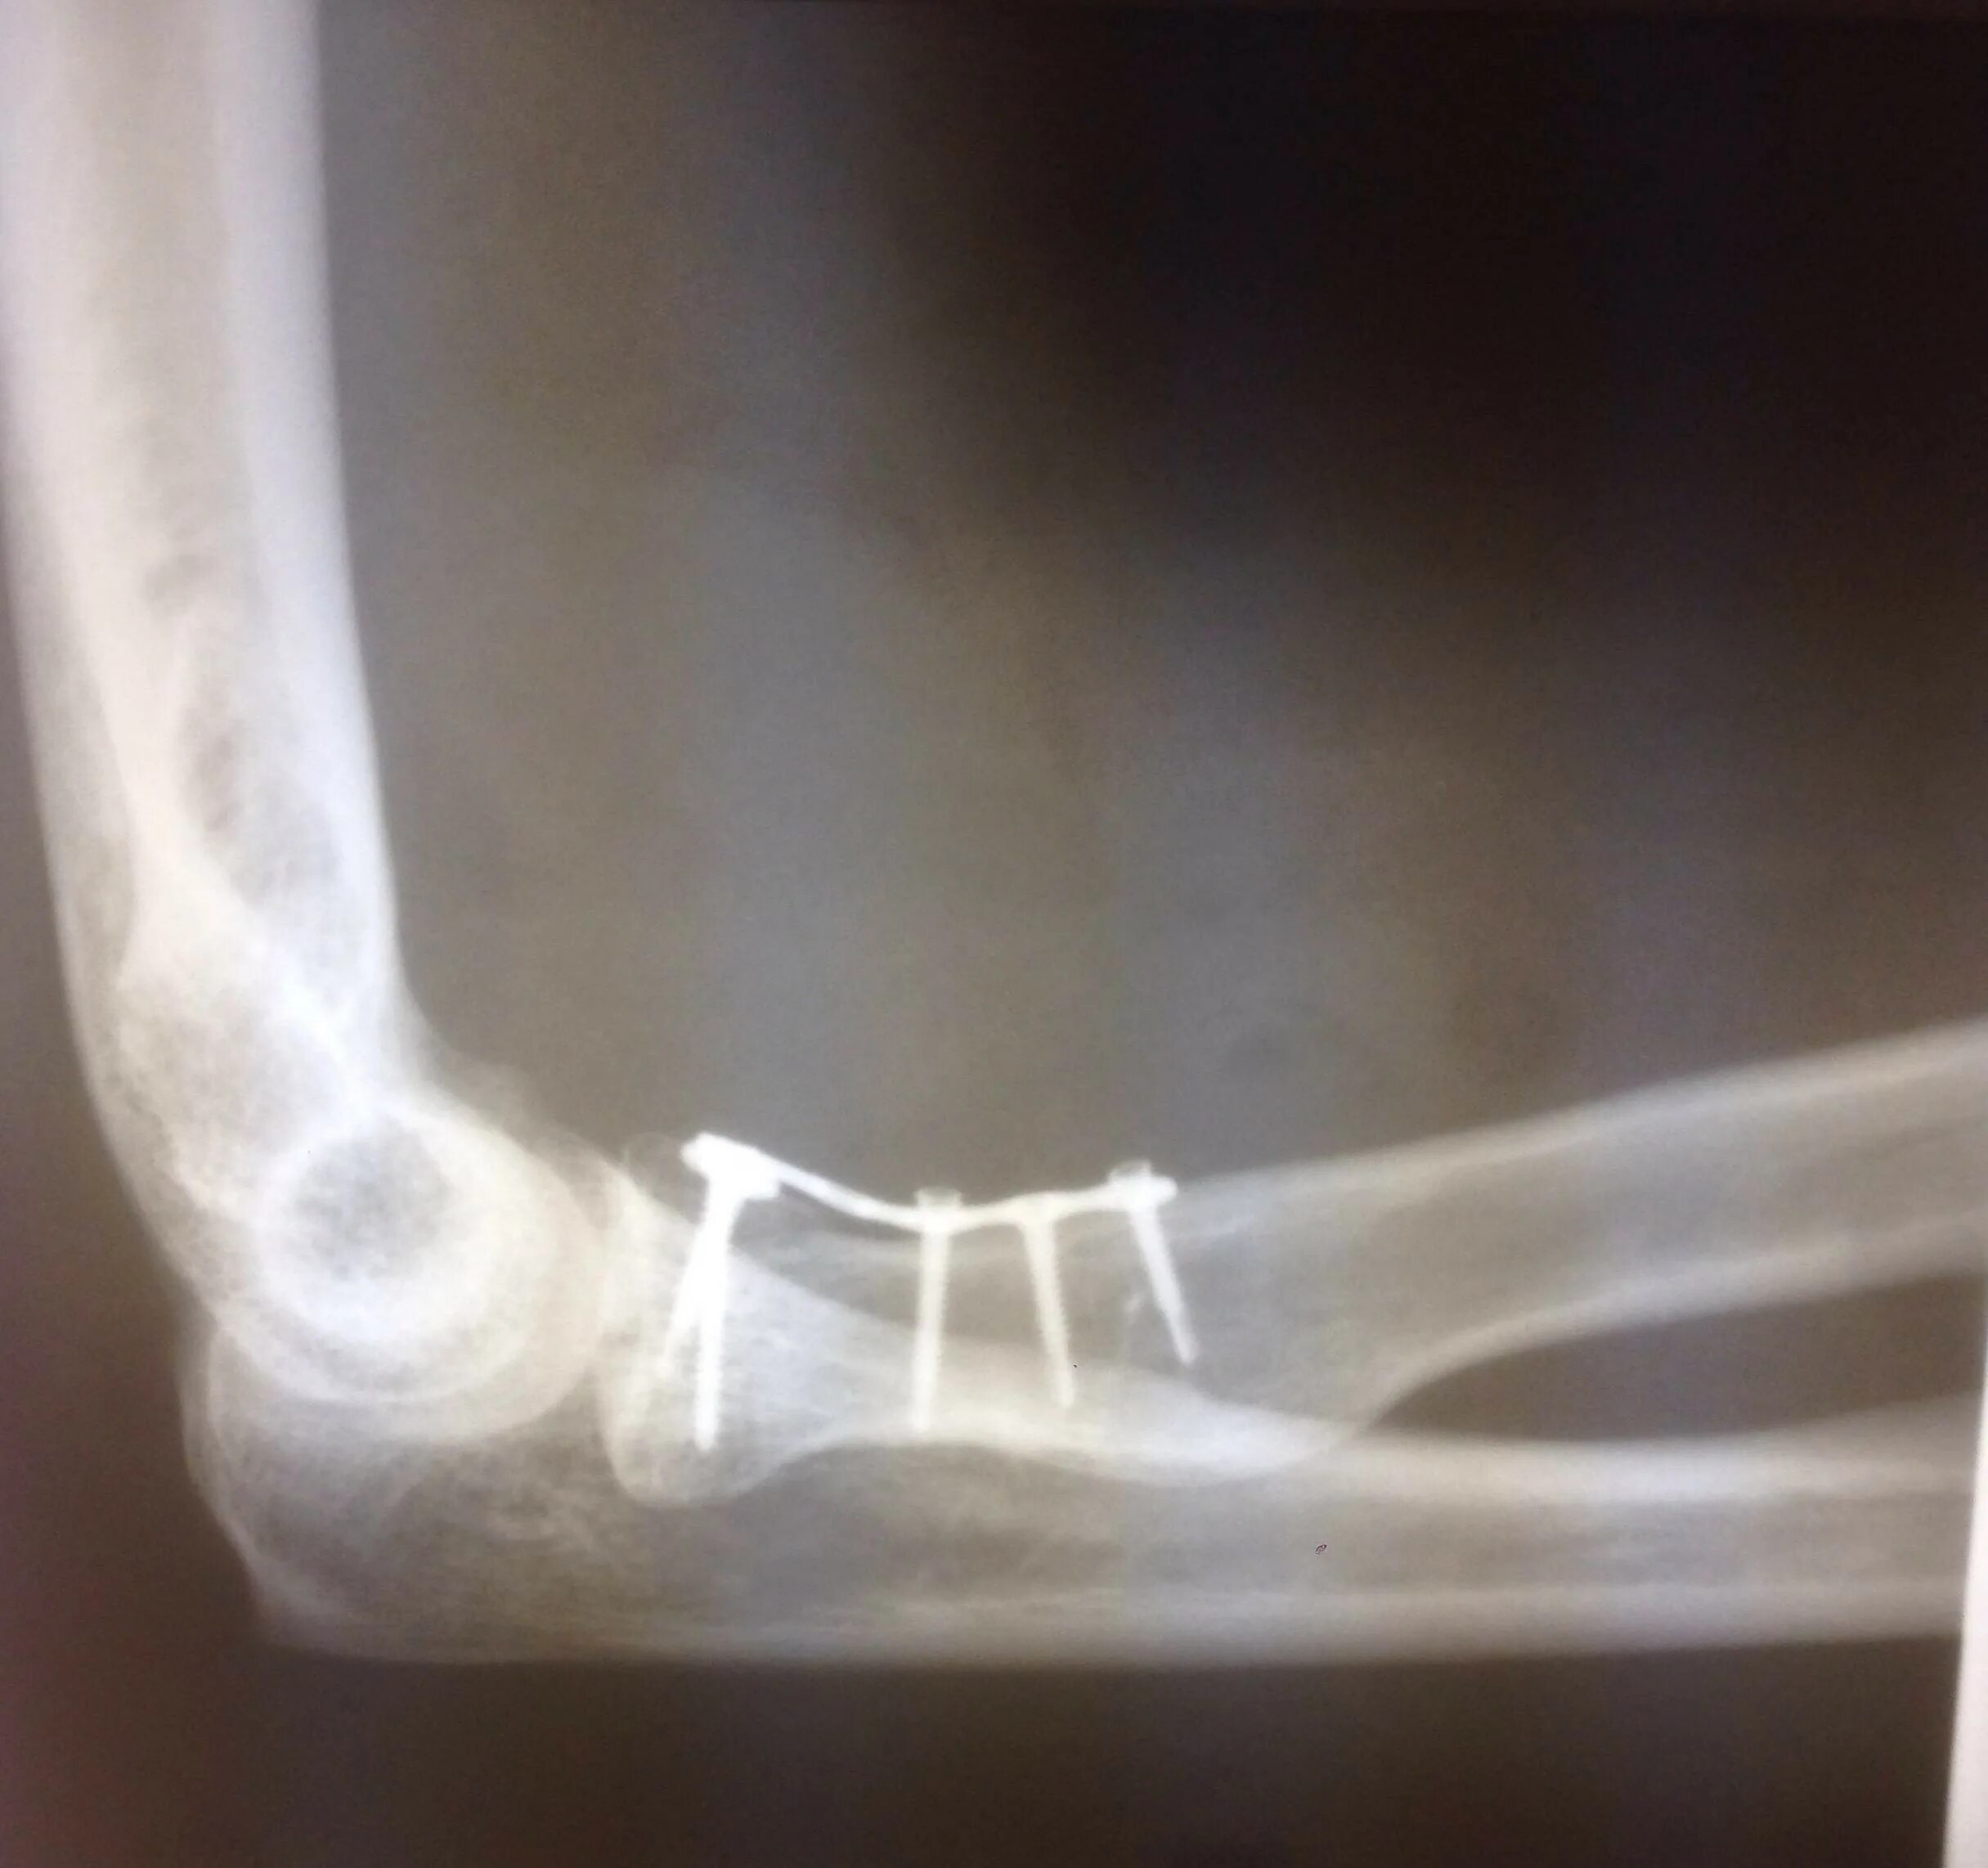

Перелом локтевой сустав мкб 10